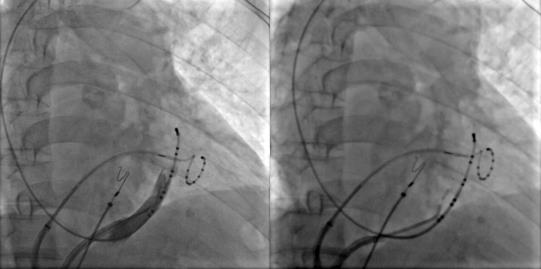

術(shù)前腔內(nèi)電圖可見(jiàn)毫無(wú)規(guī)律的房顫波,接著穿刺房間隔建立左房通路。完成肺靜脈隔離及頂部線消融后房顫轉(zhuǎn)復(fù)為規(guī)律的心房撲動(dòng)。

激動(dòng)標(biāo)測(cè)提示二尖瓣峽部依賴(lài)性房撲,而在消融過(guò)程中發(fā)現(xiàn)患者肌袖比較發(fā)達(dá),進(jìn)行二尖瓣峽部線性消融后不能終止房撲,結(jié)合患者情況決定進(jìn)行Marshall靜脈酒精消融。

冠狀竇造影定位Marshall靜脈,應(yīng)用OTW球囊進(jìn)行酒精消融